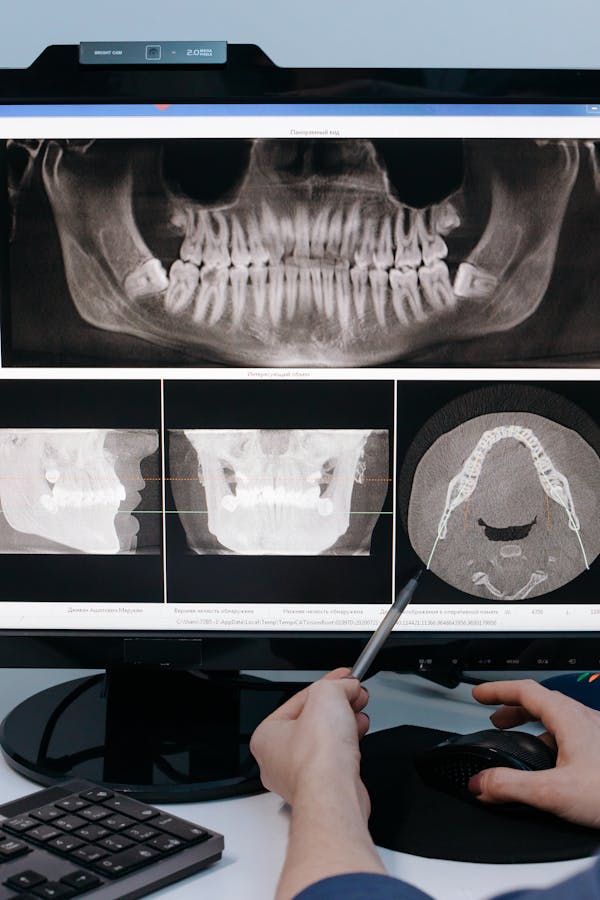

We are dedicated to providing exceptional dental care in a comfortable and welcoming environment. Our team of experienced professionals is committed to helping you achieve and maintain optimal oral health.

With state-of-the-art technology and a patient-centered approach, we offer a comprehensive range of dental services to meet all your needs. From routine check-ups to advanced procedures, we ensure every visit is a positive experience.